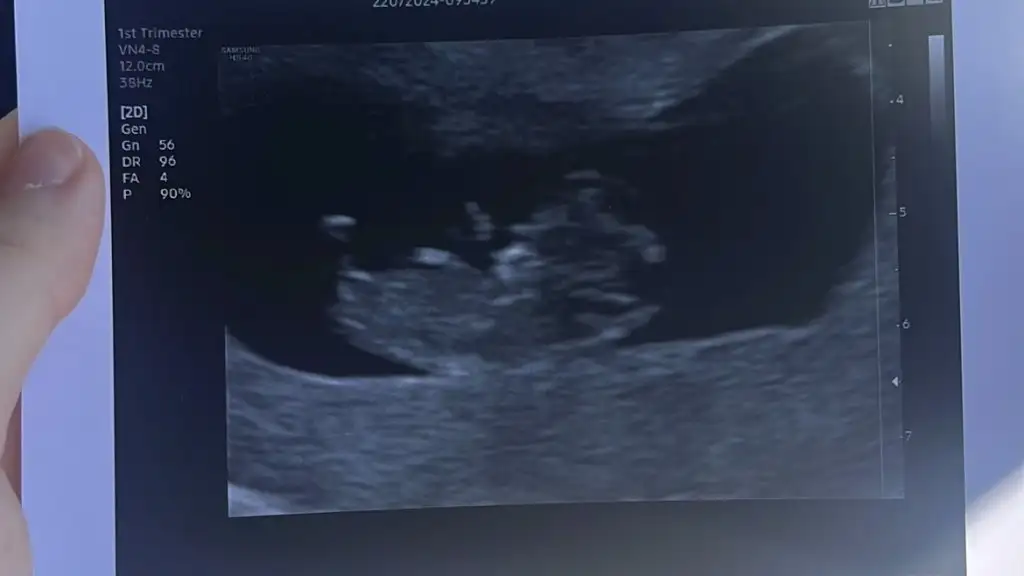

Bana da yapabilir misiniz rica etsem 12 haftalık☺️☺️

Eklentiler

• IMG_5331.webp

IMG_5331.webp

75,2 KB · Görüntüleme: 66